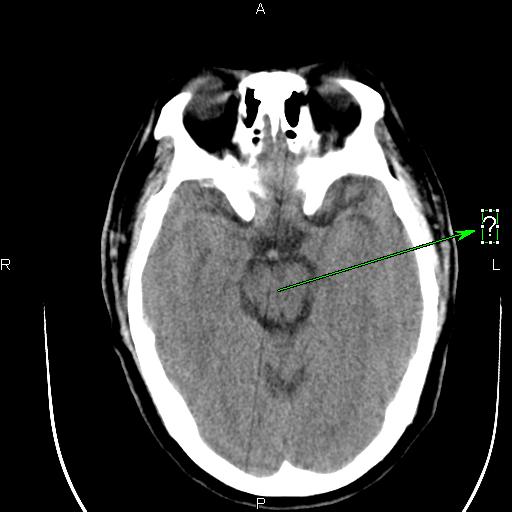

[设备故障求助] 东软ct图像伪影求助

B13F_001.jpg B13E_001.jpg B141_001.jpg B140_001.jpg

这种伪影是怎样造成的?怎样解决呢?

应该是某个通道跳起引起的直线伪影。你可以在过滤成像里检查一下,应该可以看到一跟亮线,找到是某个通道,然后屏蔽就可以了。另外一种方法就是,在ps里,不放线,不旋转,之间看所有的通道值,有没有跳起的?在ps里,放线,不旋转,这样可以看得更加清晰!你可以找到跳起的通道,或你也可以找到相应位置的das板,然后把有问题的das板换到边上,这样也可以解决问题。应该是检测器中间部位的某个das板或是通道引起的伪影